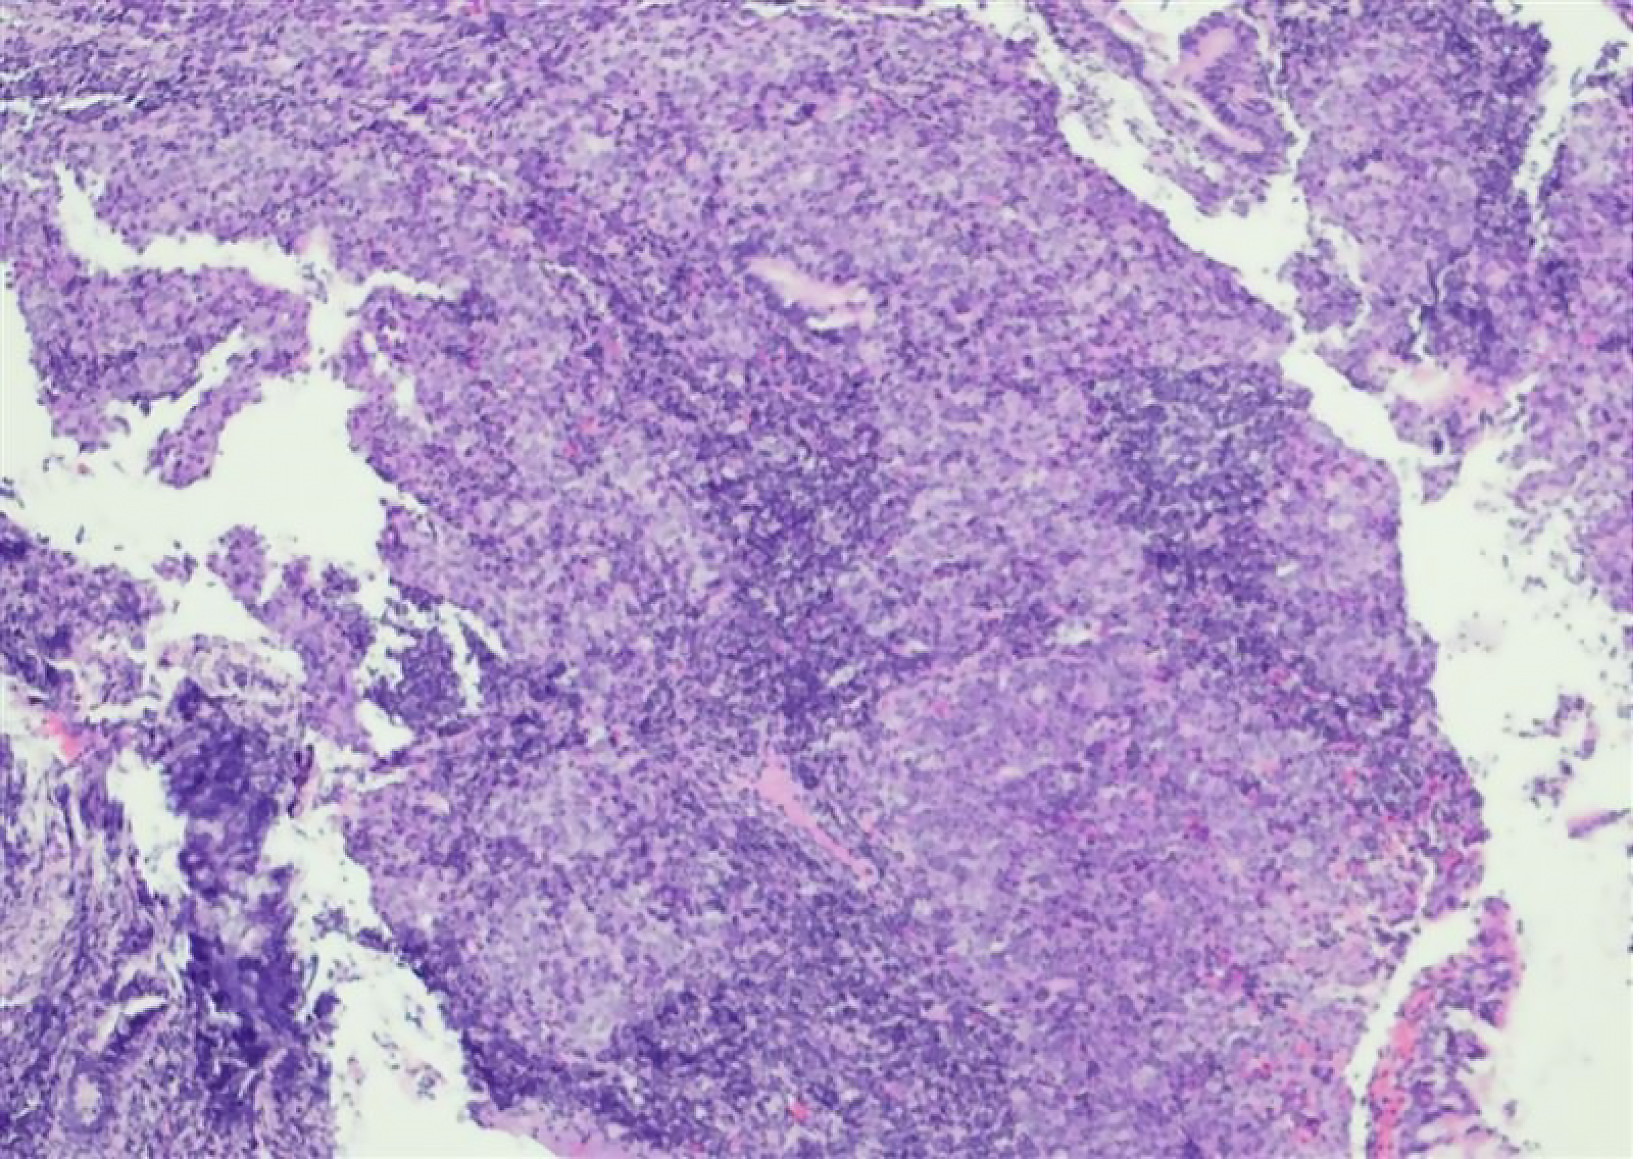

Figure 3 Pathology.

Two grayish-white to yellowish rice-grain-sized masses were obtained from the nasopharynx of the patient. Immunohistochemical analysis revealed the following results: Cytokeratin (+), tumor Protein p53 (wild-type), tumor Protein p63(+), marker of Proliferation Ki-67 (30%+), tumor Necrosis Factor Receptor Superfamily Member 8 (scattered+), ΔNp63 Isoform of tumor Protein p63 (P40) (+), Cytokeratin 7 (-), and Cytokeratin 5/6 (+). Hematoxylin and eosin staining; magnification, ×100.